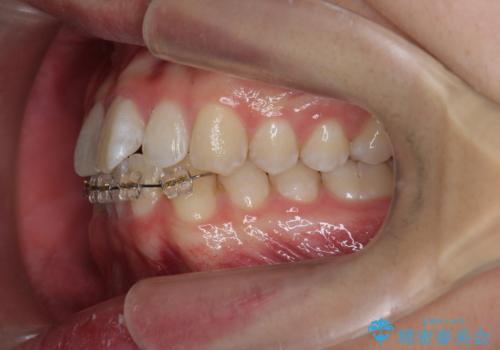

クロスバイト・歯並びが原因の歯肉退縮歯、矯正治療による審美性の改善

- 前歯の歯並び、下顎前歯の歯ぐきの下がり(歯肉退縮)の改善を求めて来院されました。

歯肉退縮の根本的な原因はすれ違った噛み合わせによる為害性のある咬合状態にあるため、歯肉退縮に対し結合組織の移植術を行うのではなく当該歯を抜去し部分矯正を含めた治療計画を立案します。

矯正治療を行ったことで、噛み合わせが安定し審美性も機能性も向上することができました。